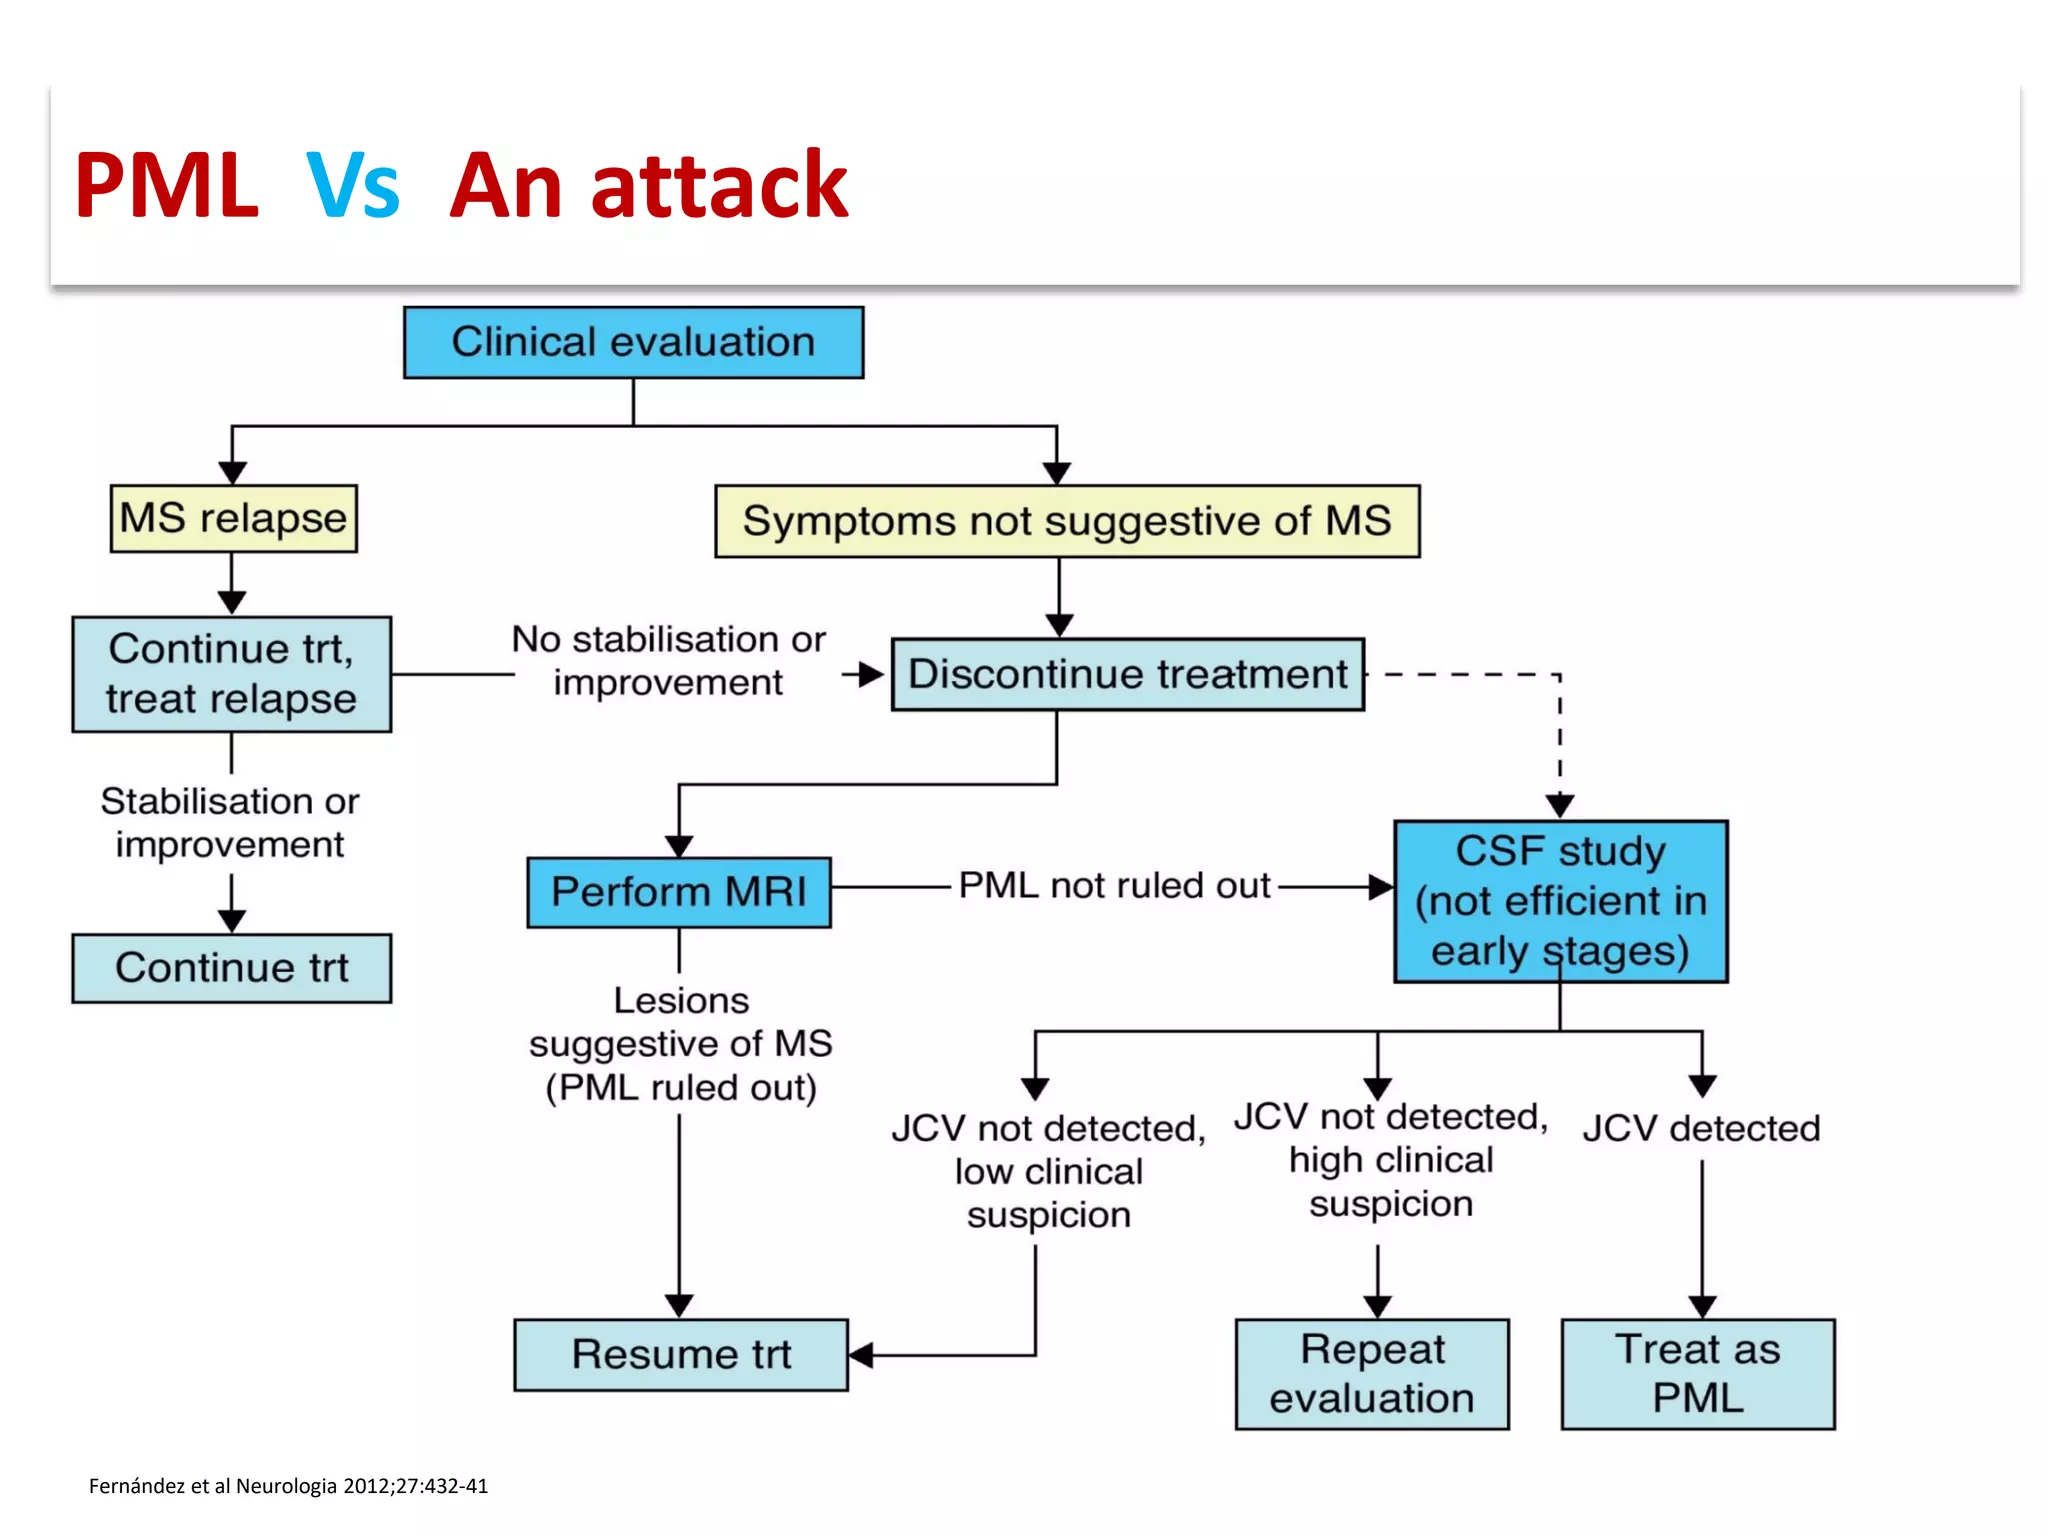

This document discusses progressive multifocal leukoencephalopathy (PML), an opportunistic infection caused by the John Cunningham virus (JCV) that leads to demyelination in the central nervous system. It highlights the epidemiology, clinical manifestations, diagnostic methods, and risk factors associated with PML, particularly in immunocompromised patients and those undergoing immunomodulatory therapies. It also presents data on the incidence of PML in patients treated with natalizumab and other therapies, addressing the relationships between these treatments and the development of PML.